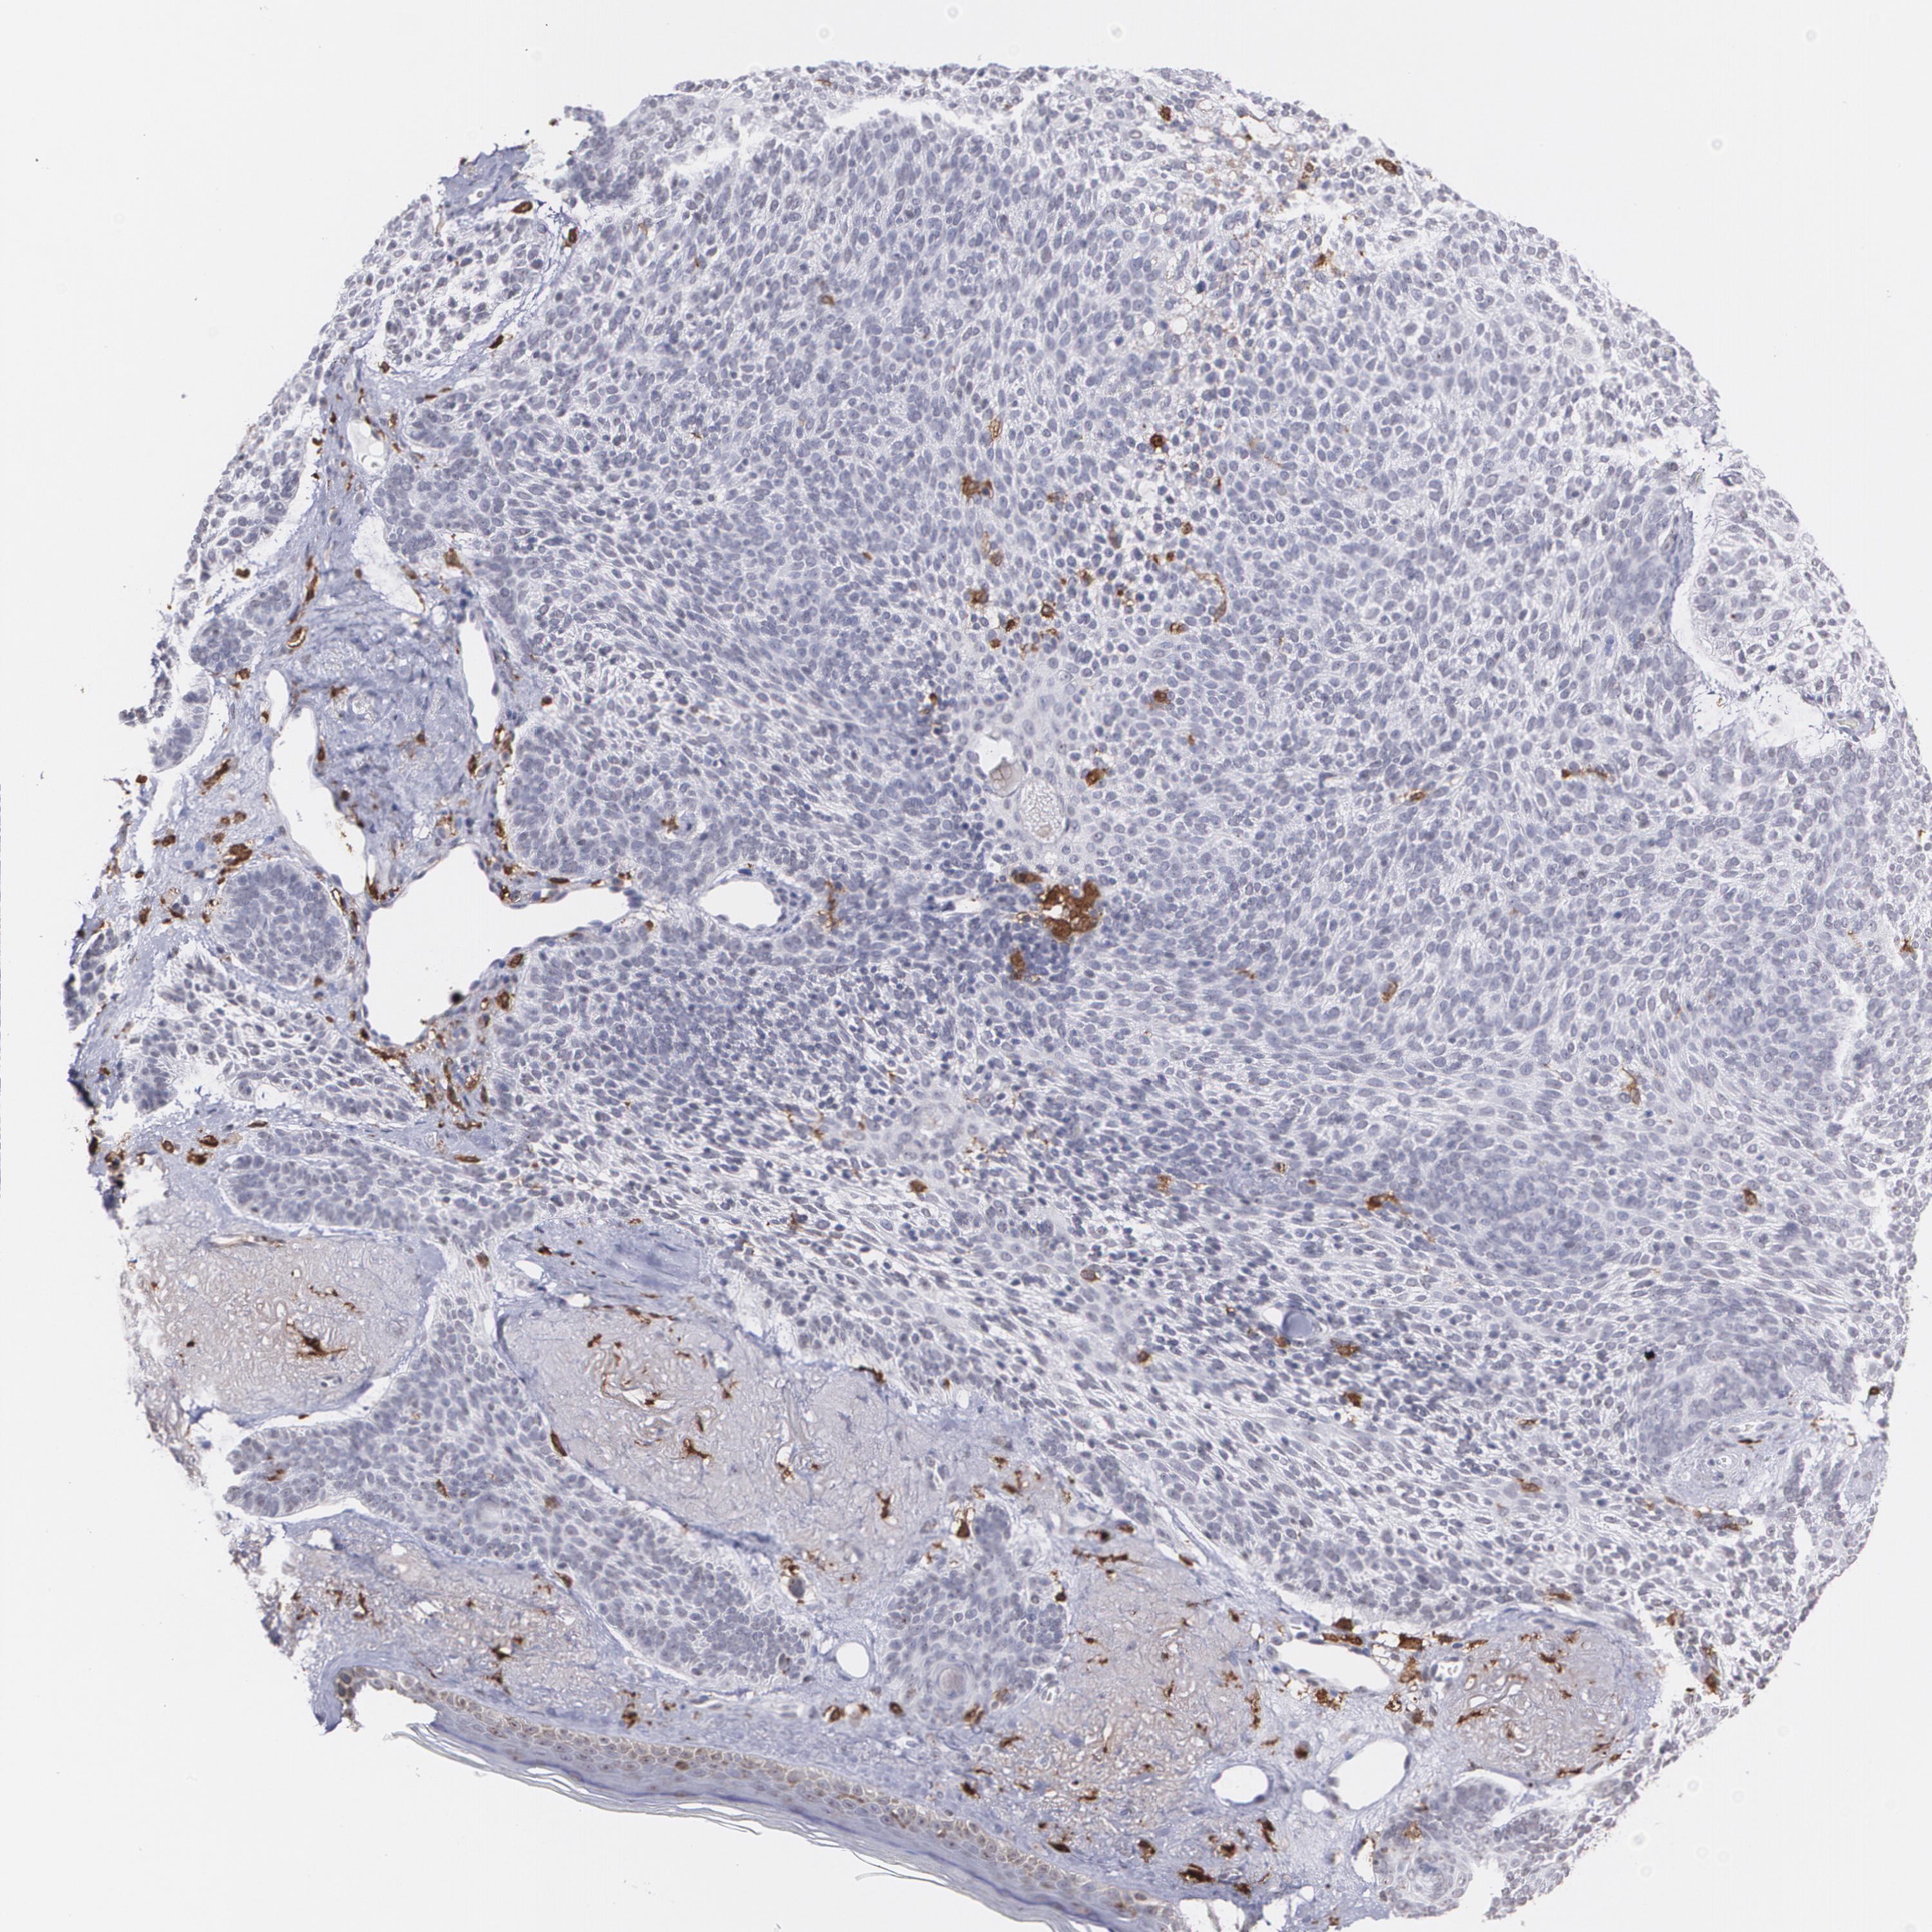

CANCER SKIN CANCER Show tissue menu

Basal cell and squamous cell cancer

SKIN CANCER - Protein expressioni

A mouse-over function shows sample information and annotation data. Click on an image to view it in a full screen mode. Samples can be filtered based on level of antibody staining by selecting one or several of the following categories: high, medium, low and not detected. The assay and annotation is described here.

Each image is clickable and will lead to virtual microscopy that enables deeper exploration of all samples and also displays staining intensity scores, fraction scores and subcellular localization as well as patient and tissue information for each sample.

Antibody HPA002327

Antibody HPA006040

Antibody CAB022160

Squamous cell carcinoma, NOS

Basal cell carcinoma